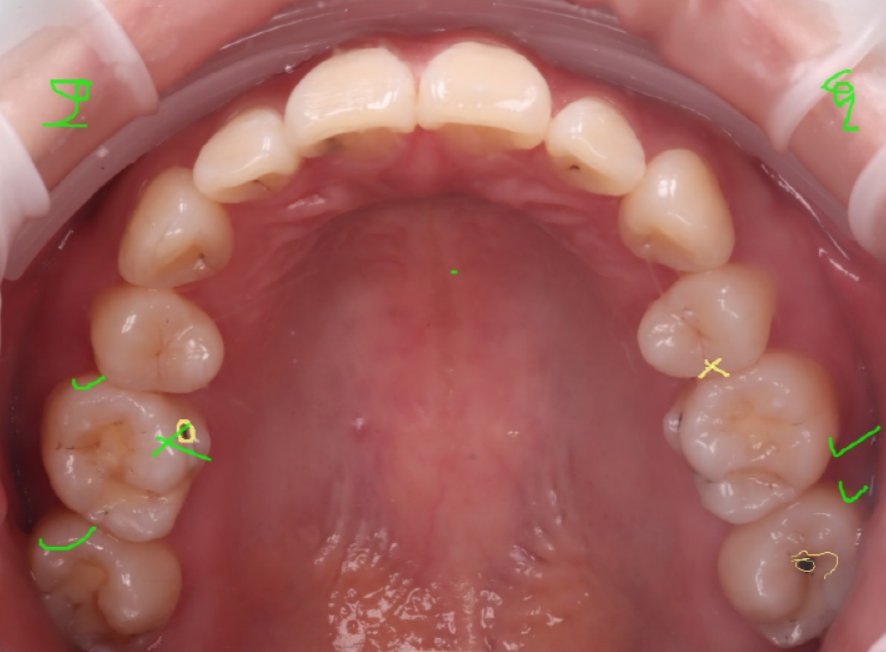

전체 구강을 살펴봤더니 왼쪽 제일 뒤어금니에도 충치가 있더라고요.

그래서 어금니(#27)도 같이 레진으로 치료하기로 했어요.

2주 뒤, 경과 체크를 위해 내원해 주셨습니다.

촬영 : 250919

큐레이로 확인해 봐도 충치가 보이지 않고 깔끔하게 완료된 것을 확인할 수 있었습니다.

그날 다시 한번 구강 내 전체를 확인해 보는데 오른쪽 아래 어금니에 미세하게 크랙이 보였습니다.

오른쪽 아래 한 개(46), 그다음은 왼쪽 아래쪽(36), 마지막으로 왼쪽 위쪽(26) 순으로 보험 적용을 받으실 수 있도록 날짜를 나눠가며 하나씩 진행했어요.